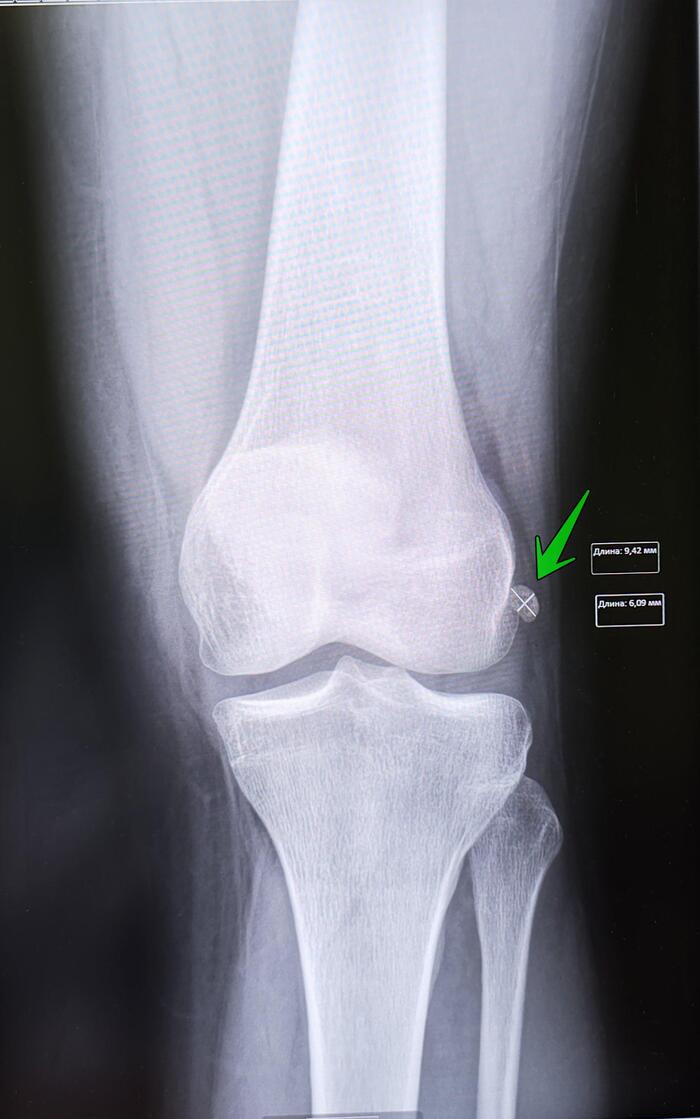

Os fabella

Фабелла — небольшая сесамовидная кость обнаруженная у некоторых млекопитающих, встроенная в сухожилие боковой головки икроножной мышцы позади латерального мыщелка бедренной кости. Это дополнительная кость, анатомическая вариация присутствующая у 39 % людей. В редких случаях таких костей бывает две или три (fabella bi- или tripartita). Эту кость можно принять за остеофит. Слово fabella — это латинское уменьшительное от слова faba, означающего «фасоль»

Описание рентгенологических снимков левого коленного сустава в двух проекциях: Суставная щель не сужена, субхондральный склероз ,остеофиты не выявлены. По заднему-латеральному краю латерального мыщелка большеберцовой кости визуализируется os fabella размером 9.4х6мм. Заключение: Данных за гонартроз слева не выявлено.Os fabella.

В редких случаях(при больших размерах os fabella) призывников с вышеописанной косточкой может беспокоить болевой синдром, в остальных случаях данная косточка никак себя не проявляет, дискомфорта не доставляет.

Категория годности призывников с os fabella-А1:годен к военной службе/ ст.10в-А2:годен к военной службе(при наличии болевого синдрома).